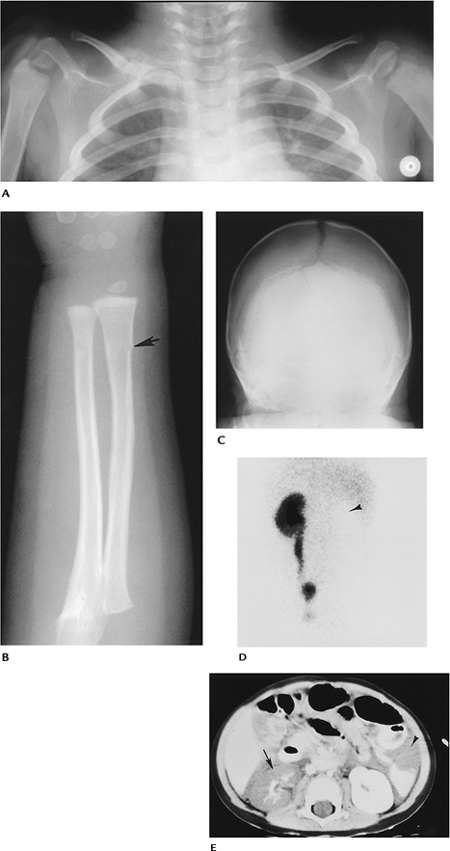

![]() |

FIGURE 15-46 Nonaccidental trauma. (A) Radiograph of the clavicles shows a fracture of the right midclavicle with abundant callus formation. (B) Radiograph of the forearm shows a subtle torus fracture (arrow). (C) AP radiograph of the skull demonstrating a skull fracture. (D) Renogram in a 14-month-old shows no perfusion in the left kidney (arrowhead). (E) CT image demonstrating fluid in the abdomen with renal (arrow) and splenic (arrowhead) injuries.

|